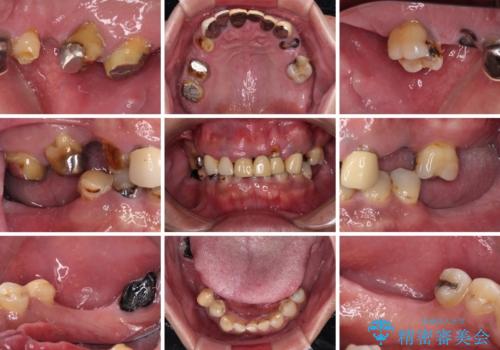

欠損と虫歯だらけの口の中 真っ白なセラミック治療

- 奥歯の欠損や、ボロボロになった歯を気にして来院された患者様です。

転勤で東京にいる1年間の間に治療を終えたいとのことで、奥歯のインプラント埋入や前歯部の歯周外科処置など、治癒に時間を要するものから始めていき、治癒期間に根管治療や補綴治療を進めて行くこととしました。